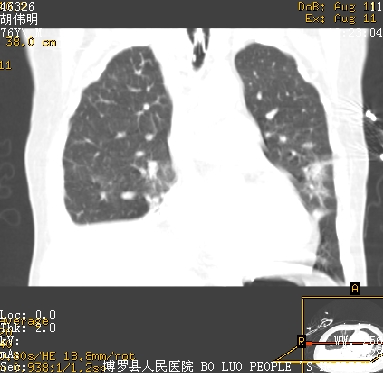

icu病人,几天都没明确诊断。m,76y,咳嗽、咳痰1周,伴气促,右胸痛入院,pe:t38.3c p135 r25 bp135/85。双肺可闻及大量湿罗音,心、腹未见明显异常。诊断:1心衰?2肺部感染?3冠心病?

11号ct

大叶性肺炎、胸腔积液

双肺感染性病变,下叶膨胀不全,胸水,左室大。

1)两肺感染性病变(右肺下叶肺脓肿可能)。2)双侧胸腔积液,以右侧为甚。

考虑双肺感染、右肺下叶肺脓肿伴双侧胸腔积液。

ards,肺感染性病变,右下叶实变,双侧胸腔积液,右侧为著,叶间胸膜积液,右上肺陈旧性tb纤维灶,左室大。